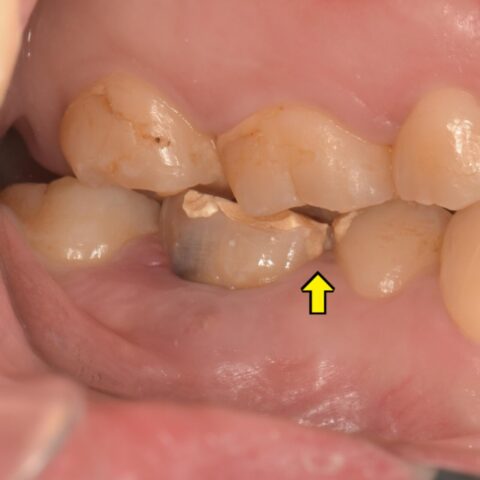

レントゲンで根の股の部分に歯質がなく、パーフォレーションがおきています。

それが原因で根尖病変ができ、骨が溶けてしまっているのでレントゲンで黒く映ります。

当院ではパーフォレーションがおきてしまった部分に「MTAセメント」をいれてリペアする治療も行っています✨